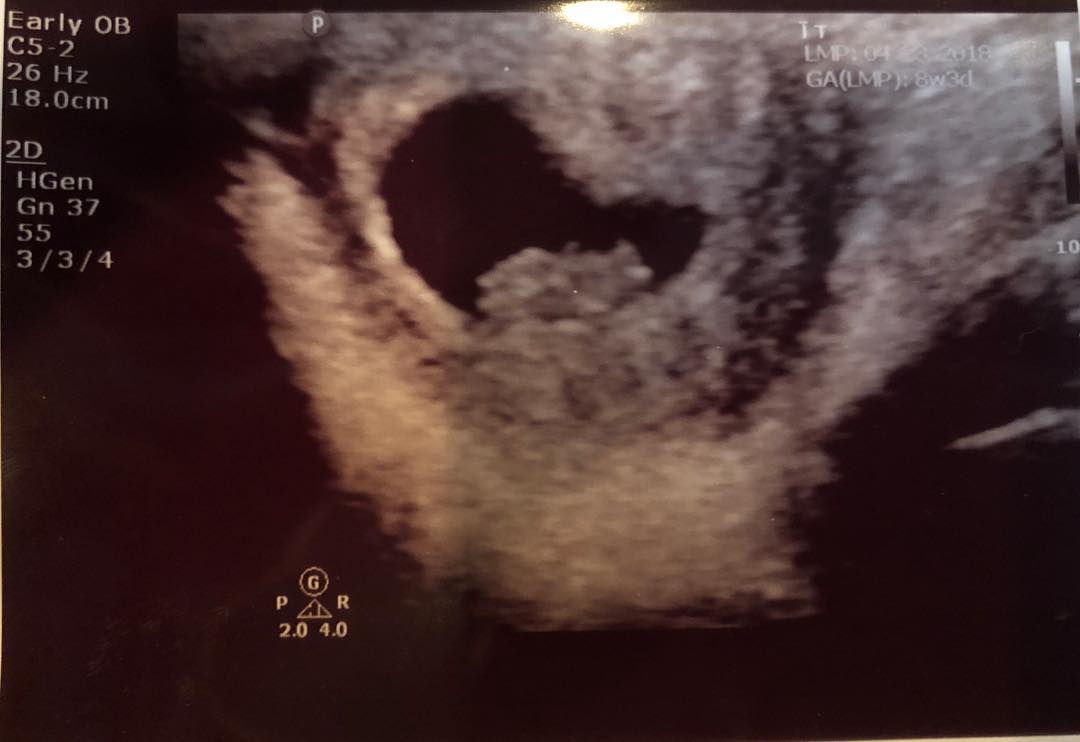

XXXTentacionの母親であるクレオパトラ・バーナードが自身のインスタグラムにエコー写真を投稿し、「彼が残してくれた最後のギフト」というコメントを添えて、XXXTentacionの恋人が子供を妊娠していることを明かした。(フロントロウ編集部)

@cleo_ohsojazzy – Instagram:「He left us a final gift.」